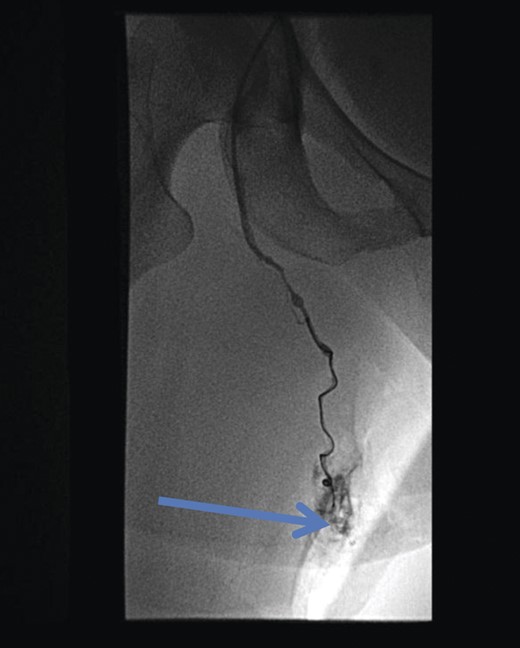

Initial investigations included duplex scan, followed by magnetic resonance scan. Duplex scanning demonstrated a competent sapheno-femoral (SFJ) and Sapheno-popliteal (SPJ) junctions bilaterally; however, did raise suspicion of a pelvic origin of the vulval varices with congested pelvic veins. Magnetic resonance venogram aided the diagnosis by demonstrating the communication of the vulval varices to the upper thigh veins with contribution from the internal iliac vein. In this case there was no evidence of ovarian varices (Fig. 1). Catheter venography was unable to confirm the contributing vein with certainty but computed pelvic venography showed a likely connection through the superficial external pudendal vein (Fig. 2).

Computed pelvic venography showing communication of thigh veins to vulval varices (blue arrow).